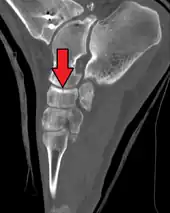

Fracture of the navicular bone

The human navicular is not a commonly broken bone but it breaks due to two reasons. The first mechanism is a stress fracture which happens commonly in athletes [7] and the other mechanism is a high energy trauma.